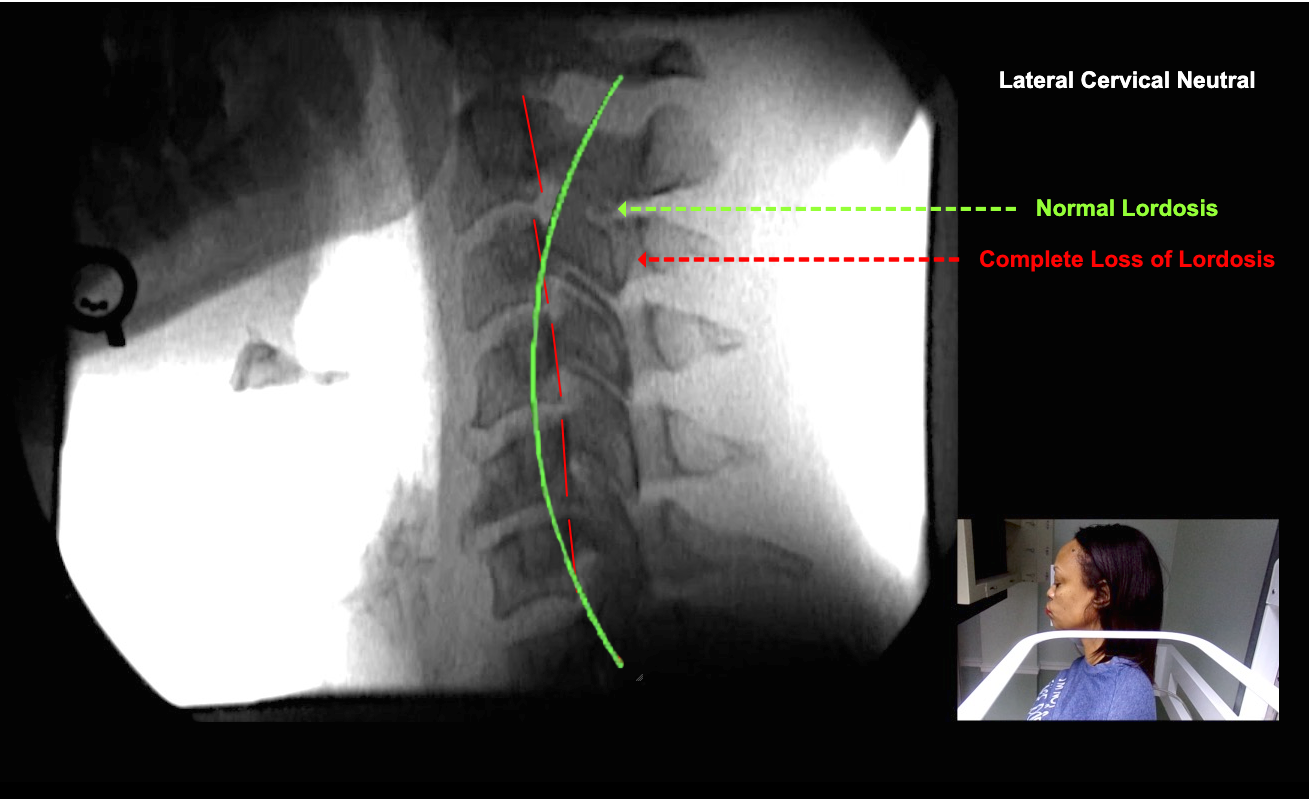

Image Name Image Type Image

Image 2